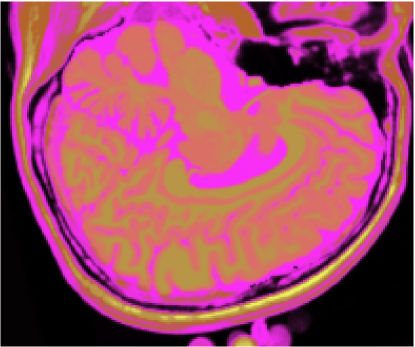

As figuras 2 (banda 0), 3 (banda 1) e 4 (banda 2) mostram a fatia 97 de um volume de imagens sagitais com 181 fatias e 0% de ruído, ponderadas em PD (densidade de próton), T1subscript𝑇1T_{1} e T2subscript𝑇2T_{2}, enquanto a figura 5 ilustra a composição colorida R0-G1-B2 da mesma fatia. Pode-se notar no topo do crânio, na parte inferior das imagens, a presença de artefatos, que podem ser resultantes de erros no simulador, mas que não são prejudiciais à análise, uma vez que, neste trabalho, não é dada ênfase à análise anatômica.

Refer to caption

Figura 5: Composição colorida R0-G1-B2 das imagens da fatia 97 ponderadas em PD, T1subscript𝑇1T_{1} e T2subscript𝑇2T_{2}

3.1 Classificadores Dialéticos Objetivos

A figura 6 mostra os resultados de classificação, enquanto a figura 7 exibe os resultados de quantização para a imagem sem ruído da fatia 97, figura 5, usando os métodos KO, CM, KM, ODC-PME e ODC-CAN. Esses resultados ilustram qualitativamente as diferenças entre os métodos de classificação e quantização, dado que a fatia 97 possui todas as 13 classes presentes na análise [51].

Figura 6: Composição colorida R0-G1-B2 das imagens da fatia 97 ponderadas em PD, T1subscript𝑇1T_{1} e T2subscript𝑇2T_{2} (a) e resultados de classificação usando os métodos KO (b), CM (c), KM (d), ODC-PME (e) e ODC-CAN (f)

Figura 7: Composição colorida R0-G1-B2 das imagens da fatia 97 ponderadas em PD, T1subscript𝑇1T_{1} e T2subscript𝑇2T_{2} (a) e resultados de quantização usando os métodos KO (b), CM (c), KM (d), ODC-PME (e) e ODC-CAN (f)